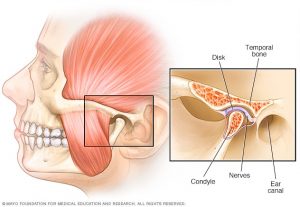

مشکلات مفصل فکی

درد و مشکلات مفصل فکی به ندرت در کودکان نیاز به درمان ارتودنسی دارد، در حالی که در بعضی از بالغین درمان ارتودنسی انگیزه اصلی مراجعه برای درمان همین مشکل است. بین رابطه دندانی و نشانه های مشکلات مفصل فکی ارتباط مشخصی نیست و لازم است که با این مسئله با دقت و احتیاط برخورد شود. درمان ارتودنسی بعضی اوقات میتواند به بیماران دارای مشکلات مفصل فکی کمک نماید، ولی نمیتوان روی رفع کامل آن حساب کرد. بیماران دارای نشانه های مشکلات مفصل فکی را می توان به دو گروه بزرگ تقسیم کرد:

اول آنهایی که مشکلات داخل مفصلی دارند، شامل جابجایی یا خرابی دیسک مفصلی.

دوم آنهایی که درد ناشی از موقعیت عضلانی دارند.

تمایز بین این دو نوع در بسیاری از بیماران مشکل میباشد. زیرا مشکلات درون مفصل و انقباضات عضلانی می توانند هر دو با هم وجود داشته باشند. با این همه وقتی قرار است درمان ارتودنسی انجام شود تمایز این دو از یکدیگر های با اهمیت است. احتمال کمی می رود ارتودنسی بتواند به بیمارانی که مشکل داخل مفصل یا درد ها با منشأ غیر عضلانی دارند کمک زیادی کند. از طرف دیگر آنهایی که درد و مشکلات عضلات اطراف مفصل فکی را دارند ممکن است با درمان ارتودنسی و بهبود روابط دندانی بهتر شوند. در اکثر مردم به تدریج که رشد می کنند بعضی نشانه های بیماری مفصل فکی ظاهر میشود و تعجب آور نیست اگر بعضی اوقات مفصل ها تغییراتی پیدا کنند. به احتمال زیاد در بیمارانی که رماتیسم سایر مفاصل را دارند، نشانه های مشکلات مفصل فکی ناشی از التهاب مفصل فکی است. در بیمارانی که تنها در مفصل فکی دارای نشانه و مشکل می باشند حتی اگر رادیوگرافی ها مشکلات مفصل را نشان دهد، باید به وجود درد و انقباضات عضلانی مشکوک گردید.

جابجایی دیسک مفصل فکی میتواند به علل زیادی پیش آید یکی از علل صدمه به مفصل و کشیده شدن یا پاره شدن الیاف پشت مفصل می باشد. در این صورت انقباض عضله به هنگام باز شدن زیاد فک و جلو آمدن فک، دیسک مفصل را به جلو می کشد، ولی وقتی که فک بسته میشود این الیاف وجود ندارند که دیسک را به محل اولیه بر گردانند، نتیجه چنین پدیده ای ایجاد صدا به هنگام باز و بسته کردن دهان می باشد، زیرا وقتی که بیمار دهان خود را باز میکند مفصل با ایجاد صدا از روی سر فک پایین عبور می کند و وقتی که دهان بسته میشود به سمت جلو جابه جا می گردد.